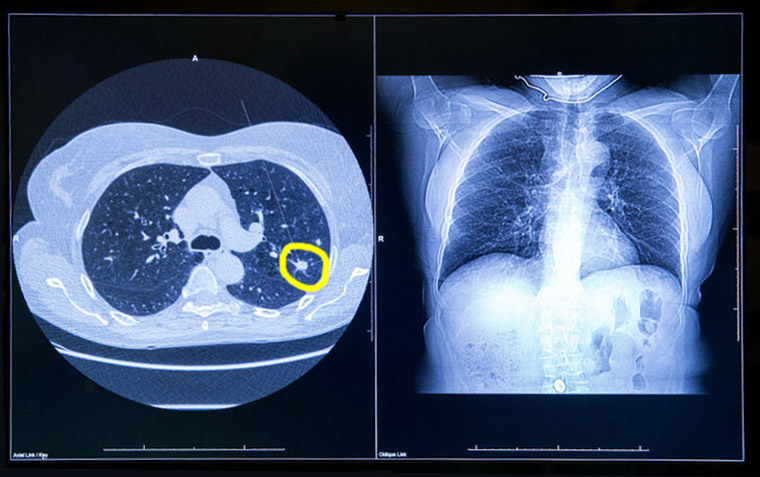

Detección del cáncer de pulmón mediante TAC de baja dosis en Francia: resultados finales del estudio DEP KP80

Este estudio demostró la viabilidad y eficacia del cribado del cáncer de pulmón en un contexto de la vida real, en el que la mayoría de los cánceres de pulmón se diagnostican en una etapa temprana y se extirpan quirúrgicamente. Nuestros resultados también destacaron la importancia de la participación en cada ronda, subrayando el hecho de que optimizar la organización es un objetivo principal. eBioMedicine, noviembre de 2024.